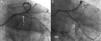

An 83-year-old man with hypertension, bilateral carotid disease, porcelain aorta and moderate renal failure was admitted with non-ST-elevation myocardial infarction. Coronary angiography revealed three-vessel disease with distal left main (LM) bifurcation involving the ostia of both the left anterior descending (LAD) and the left circumflex (LCx) coronary arteries (Medina 0,1,1; SYNTAX score 23) (Figure 1). The patient was considered unsuitable for surgery. Optical coherence tomography (OCT)-guided percutaneous coronary intervention (PCI) was undertaken. Pullbacks from the LAD and LCx (Figure 2) were obtained using frequency-domain OCT (ILUMIEN OPTIS PCI Optimization System, St. Jude Medical, St. Paul, MN). The OCT findings confirmed proximal LAD and LCx stenosis with ostial involvement, without significant disease in the LM. Moreover, the carina showed the “eyebrow” sign, indicating a risk of plaque shifting. Non-simultaneous V-stenting of both LAD and LCx was the chosen technique. After stenting the LAD (3.0/38 mm drug-eluting stent), plaque shifting to the LCx was evident on coronary angiography (Figure 3A). A 3.5/16 mm drug-eluting stent was implanted in the LCx, with final kissing balloon (Figure 3B). Pullback with real-time 3D reconstruction from the LCx revealed the V-stenting with correctly apposed struts and protruding only slightly into the LM (Figure 4).

Pullbacks from (A) left anterior descending (LAD) and (B) left circumflex (LCx) arteries with 3D reconstruction; (C) distal left main (LM) before LAD and LCx ostia showing no significant stenosis (area 12 mm2). Carina with “eyebrow” shape, leading to plaque shift (see also Figure 3). *: carina; **: marginal branch.